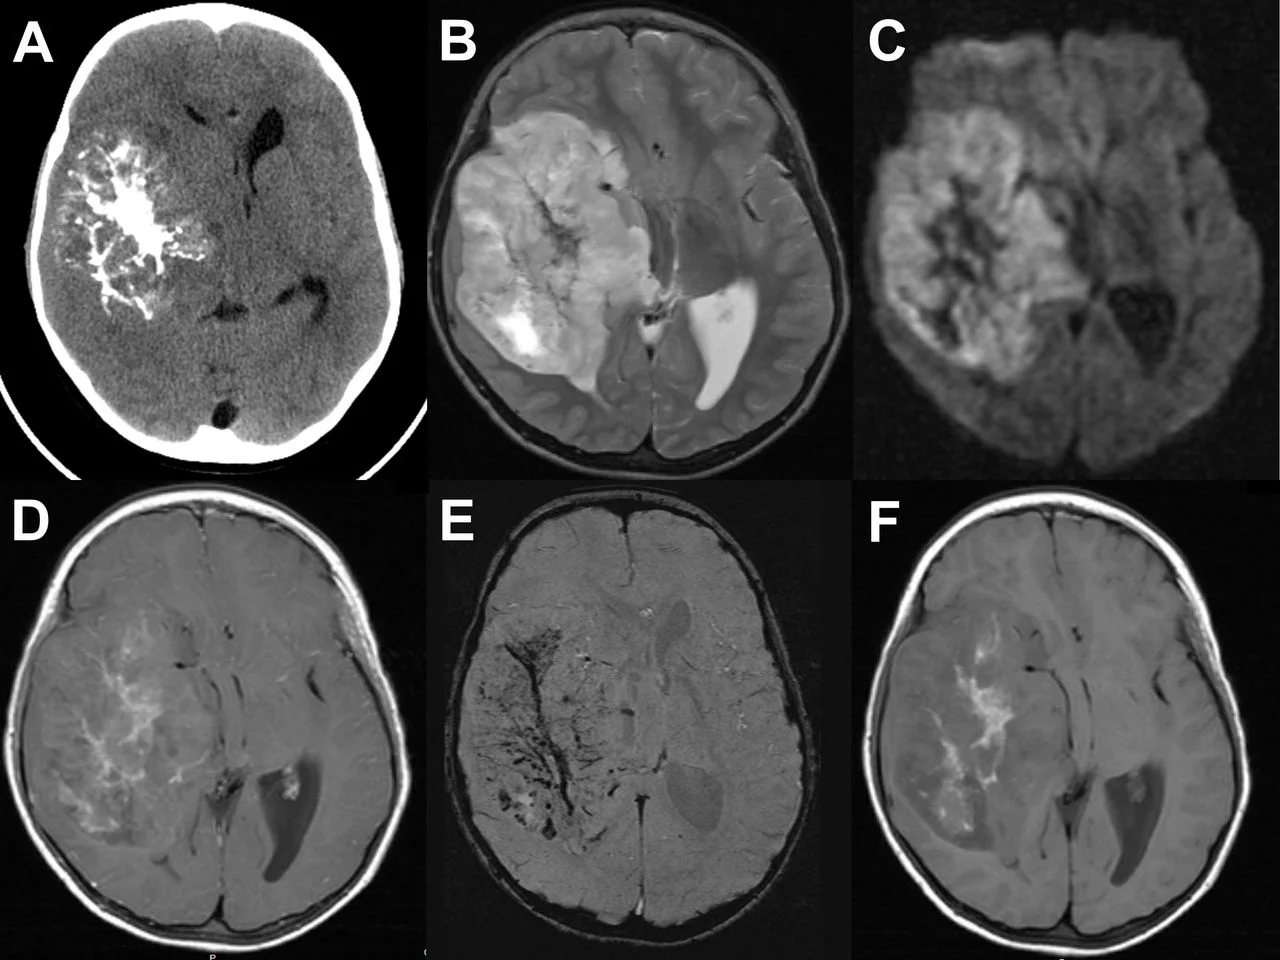

Πώς γίνεται η διάγνωση & ποιος ο ρόλος της MRI;

Η μαγνητική τομογραφία είναι το βασικό διαγνωστικό εργαλείο, στις περισσότερες περιπτώσεις απαραίτητη είναι η ιστολογική επιβεβαίωση.

Η διερεύνηση περιλαμβάνει:

-

Μαγνητική τομογραφία εγκεφάλου (MRI) με και χωρίς σκιαγραφικό, συνήθως

σε πολλαπλές ακολουθίες. Η MRI:

- καθορίζει με ακρίβεια την εντόπιση και την έκταση του όγκου,

- βοηθά στην εκτίμηση αν είναι χαμηλής ή υψηλής κακοήθειας (μορφολογία, αιμάτωση),

- ανιχνεύει συνοδό υδροκεφαλία ή πιεστικά φαινόμενα.

- Εξειδικευμένες τεχνικές MRI (π.χ. perfusion, spectroscopy) μπορούν να βοηθήσουν στη διάκριση χαμηλού από υψηλού βαθμού όγκο.